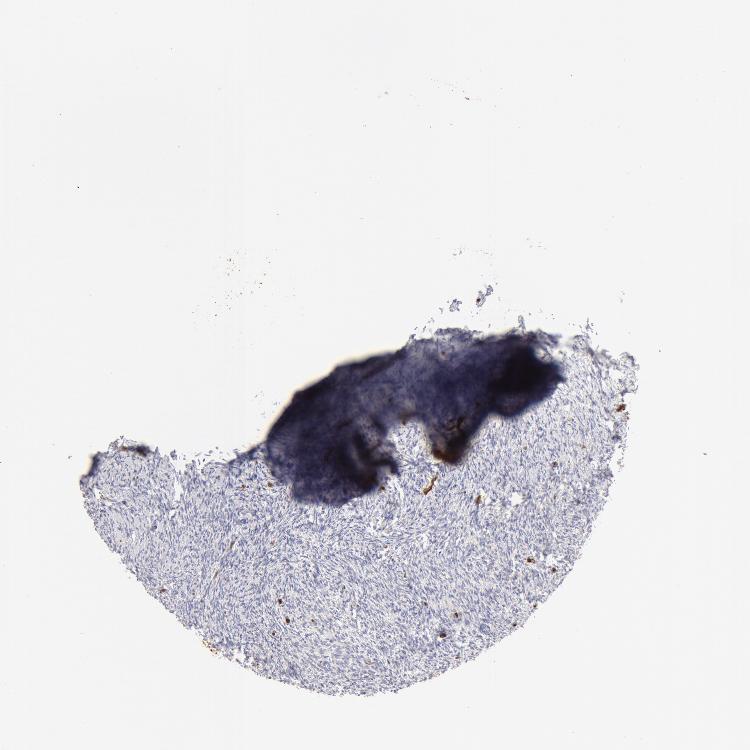

OVARY - Antibody stainingi

Antibody staining in the annotated cell types in the current human tissue is reported as not detected, low, medium, or high, based on conventional immunohistochemistry profiling in selected tissues. This score is based on the combination of the staining intensity and fraction of stained cells.

Each image is clickable and will lead to virtual microscopy that enables deeper exploration of all samples and also displays staining intensity scores, fraction scores and subcellular localization as well as patient and tissue information for each sample.

Antibody HPA019206Antibody CAB001707

Follicle cells -Medium

Ovarian stroma cells Not detectedNot detected